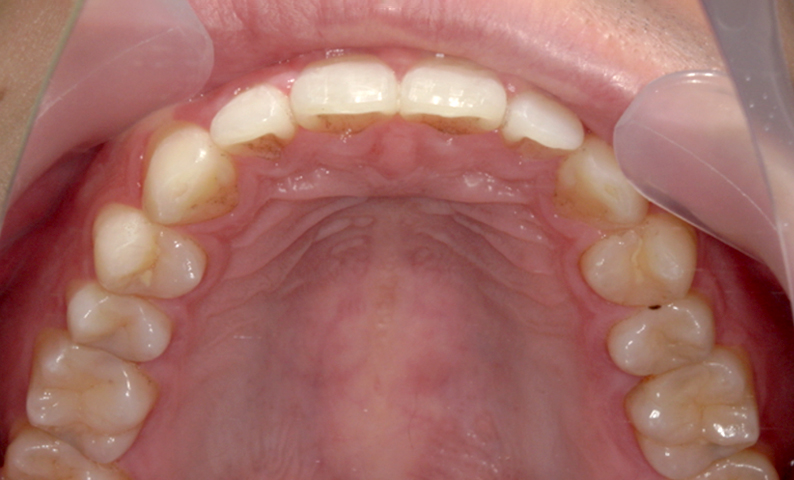

| 治療前 | 治療後 |

|---|---|

|